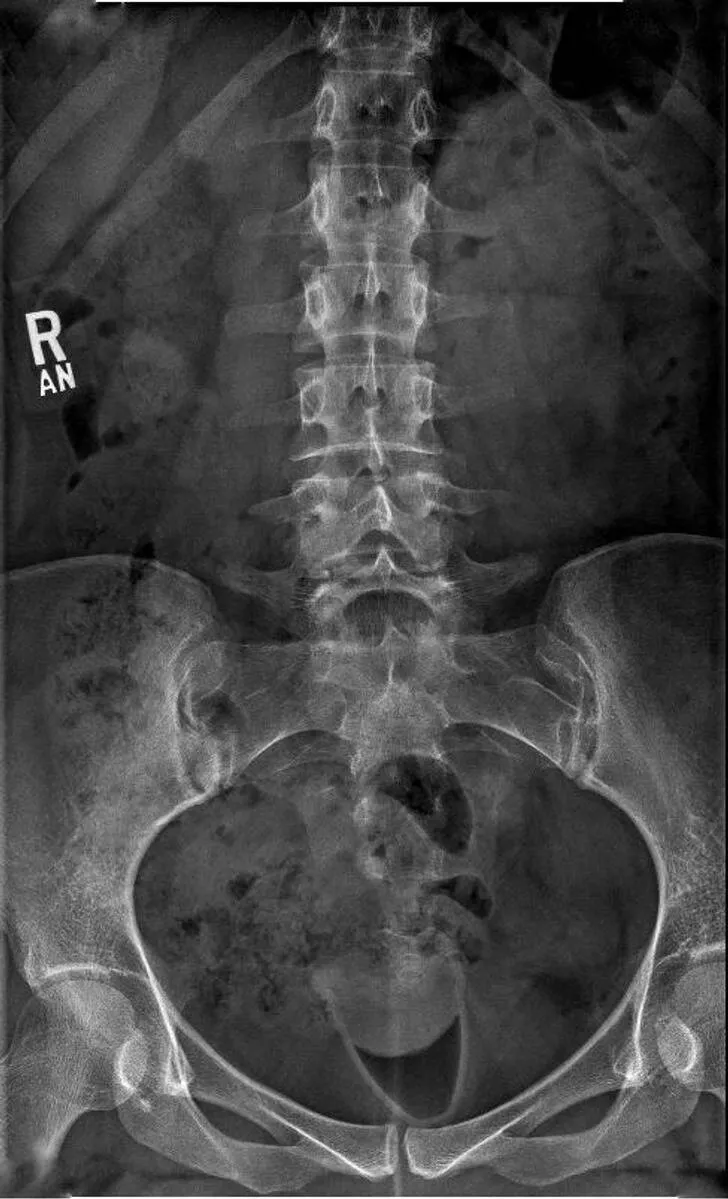

#27 Had an X-ray while wearing a menstrual cup.